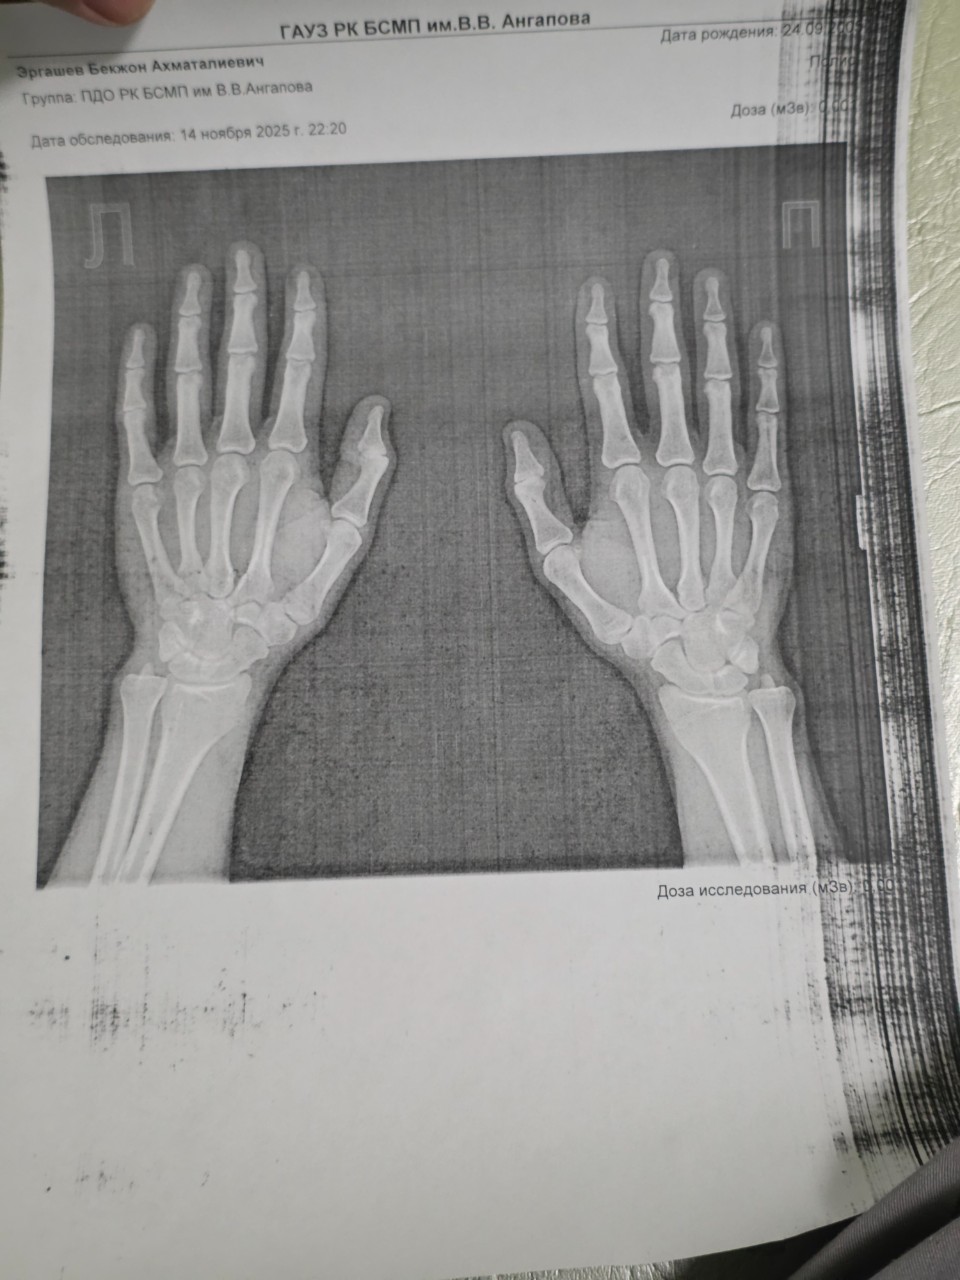

Спрашивает: Бекжон

Пол: Мужской

Возраст: 20 лет

Здравствуйте, я хотел бы узнать открытый ли у

меня зоны роста и узнать, если они открыты, на

сколько еще смогу примерно вырасти. Мой рост

на данный момент 172 см. Спасибо за ответ!